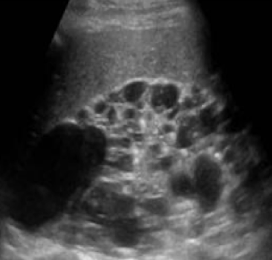

SONO: medullary cystic kidney disease (MCKD)

hyperechoic calyces with or without stones

??

medullary cystic kidney disease

calcium deposits in calyces